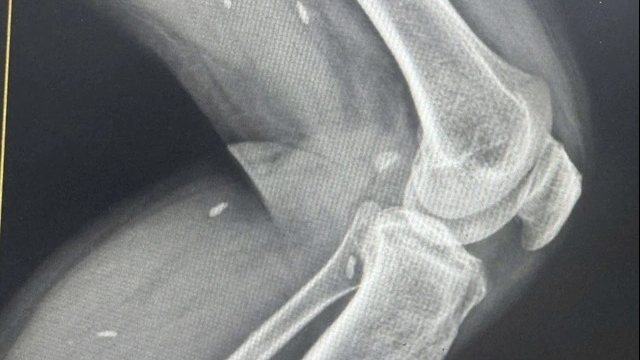

Kết quả xét nghiệm có số lượng tiểu cầu tăng, xét nghiệm đánh giá tổn thương tế bào gan tăng cao, xét nghiệm CRP để xác định và đánh giá tình trạng viêm hoặc nhiễm trùng tăng; Xét nghiệm chẩn đoán bệnh giang mai (TPPA) tăng cao với kết quả 1:20480, tức dương tính. Do vậy, bác sĩ chẩn đoán xác định bé bị giang mai bẩm sinh trong sự lo lắng, bất ngờ của cả gia đình.